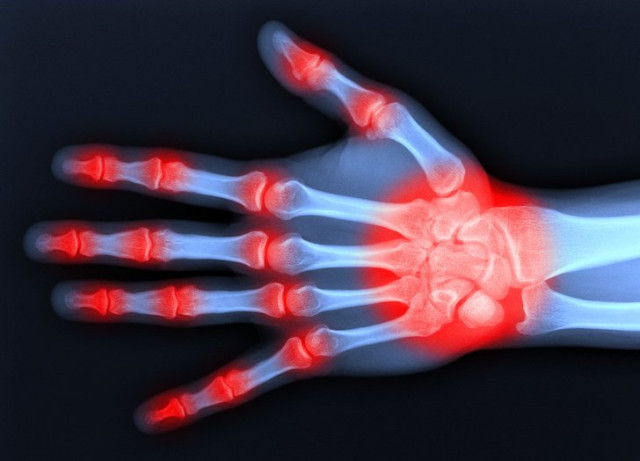

Ревматоїдний артрит навчаться не лише лікувати, а й передбачати

Ревматоїдний артрит – хвороба, при якій люди страждають хронічним запаленням суглобів, яка зачіпає, як правило, коліна, кисті рук, щиколотки, гомілковостопні суглоби. Поки що причини її появи невідомі, а лікування виключно симптоматичне. Однак на початку 2019 року вчені розповіли про ген ELMO1, який може стати ключем до позбавлення від ревматоїдного артриту, оскільки його відключення знижує запалення. В даний час медики шукають препарат, здатний відключати ген, а також розробляють способи його виявлення в організмі людини, що допоможе боротися з хворобою на ранніх стадіях.